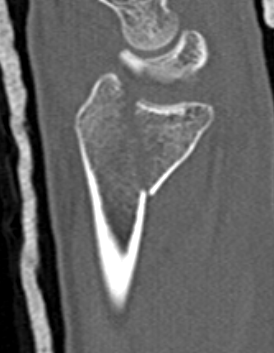

Unacceptable reduction

1.  Distal radial Step > 2mm

- leads to RC OA radiographically

- not proven to lead to dysfunction

Distal Radius Fracture Articular Step Coronal CTDistal Radius Fracture Articular Step Sagittal CT

5.  Sagittal tilt

- > 15o dorsal

- > 20o volar